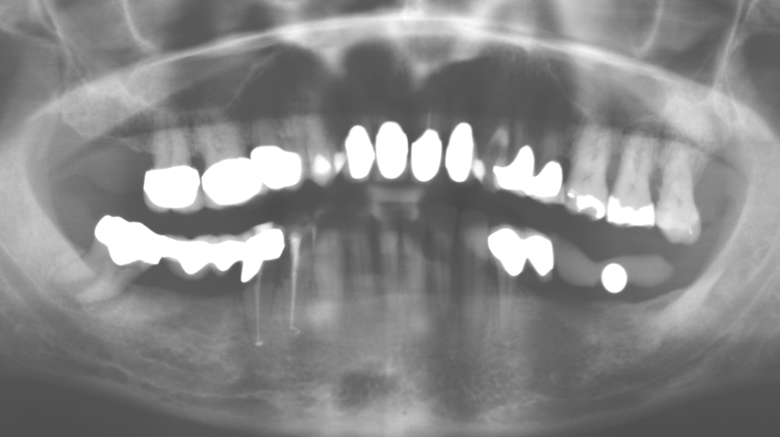

Eine 52-jährige Patientin stellte sich nach Zahnverlust im 3. Quadranten erstmals 2004 vor. Sie hatte den Wunsch nach einer prothetischen Neuversorgung. Im Rahmen der parodontologischen und radiologischen Diagnostik zeigte sich ein ausgeprägter parodontologischer Behandlungsbedarf. Die Zähne 48, 28, 27 zeigten zudem eine infauste Prognose und wurden entfernt (Abb. 1). Nach der erfolgreich abgeschlossenen systematischen PARTherapie wurde eine festsitzende implantatprothetische Versorgung mit Insertion von fünf Implantaten in Regio 35, 36, 37 und 46, 47 durchgeführt. Die prothetische Versorgung der natürlichen Zähne erfolgte mit verblendeten Zirkonoxidkeramikkronen, die Implantate wurden mit zweiteiligen individuellen Zirkonoxidabutments und ebenfalls verblendeten Kronen aus einer Zirkonoxidkeramik versorgt (Cercon base colored, Dentsply Sirona Lab). Die definitive Insertion der prothetischen Versorgung erfolgte im Jahr 2005.

Aufgrund der bestehenden parodontalen Vorerkrankung erfolgte die unterstützende Parodontaltherapie (UPT) in den ersten Jahren in einem DreiMonatsIntervall. Dabei zeigte die Patientin eine hohe Motivation und gute Compliance. Bei den jährlich erhobenen Sondierungsbefunden zeigten sich stabile parodontale Verhältnisse mit einem BOPIndex unter fünf Prozent. Aufgrund der stabilen parodontalen Situation und der guten Mitarbeit der Patientin wurde ab dem sechsten Jahr der prothetischen Funktionsphase das Recallintervall auf halbjährlich umgestellt. Auch mit diesem veränderten Recallintervall zeigten sich bei der jeweils jährlichen Aufnahme des Parodontalstatus stabile parodontale Verhältnisse, ohne Zunahme der Sondierungstiefen und einem BOPIndex unter fünf Prozent (Abb. 2a und b).

Im Rahmen der ZehnJahresKontrolle zeigten sich keine Hinweise auf einen fortschreitenden parodontalen Attachmentverlust oder einen periimplantären Knochenverlust (Abb. 3).